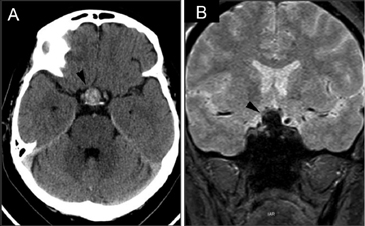

A diferencia de la tomografia computada, que emplea tubos de rayos X, la RM no utiliza radiaciones ionizantes, lo que es una ventaja a considerar en los pacientes pediátricos y en las mujeres embarazadas. La RM tiene una excelente resolución espacial y de tejidos blandos; por ejemplo permite precisar la presencia o ausencia de la neurohipófisis, lo que no es posible con la Tomografia Computada5-7. Con la TAC, con o sin medio de contraste yodado, es posible detectar microadenomas y macroadenomas pituitarios (Figuras 1A y 1B); sin embargo, en los macroadenomas puede ser difícil distinguir las relaciones del tumor con el quiasma óptico, o definir la invasión del seno cavernoso. Además, los artefactos producidos por amalgamas dentales deterioran las imágenes y la dificultad para lograr posiciones cómodas para los pacientes, con el fin de obtener cortes coronales directos, limitan la utilidad de la TAC.

Figura 1A y B. TAC con contraste yodado, corte coronal, muestra un microadenoma lateralizado a izquierda (punta de flecha). Control a los 2 años. TAC con contraste yodado, corte coronal, demuestra aumento de volumen del microadenoma, lo que es infrecuente de observar en clínica (punta de flecha).